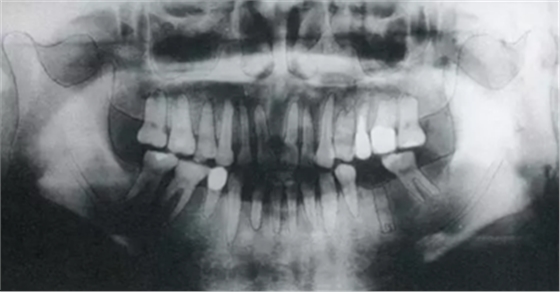

▲圖6-1

頰側角化齦較少,頰系帶高位附著。

▲圖6-2

同時期的曲面斷層片。

▲圖6-3

種植體植入后的X光片